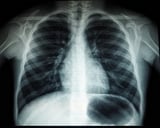

Led by Wake Forest University and UNC, a large randomized clinical trial involving over 26,000 smokers evaluated the effectiveness of the digital health platform mPATH-Lung, which offers education, decision aids, and appointment requests outside of traditional clinical settings.

In the trial, 1,333 eligible smokers used the mPATH-Lung program, resulting in a significant increase in screening rates, with 24.5% completing a lung cancer screening CT scan within 16 weeks, compared to 17% in the control group.

A multi-site randomized trial published in JAMA demonstrated that the digital program increased lung cancer screening completion from 17% to 25% among high-risk individuals within 16 weeks, showing a substantial boost in screening uptake.